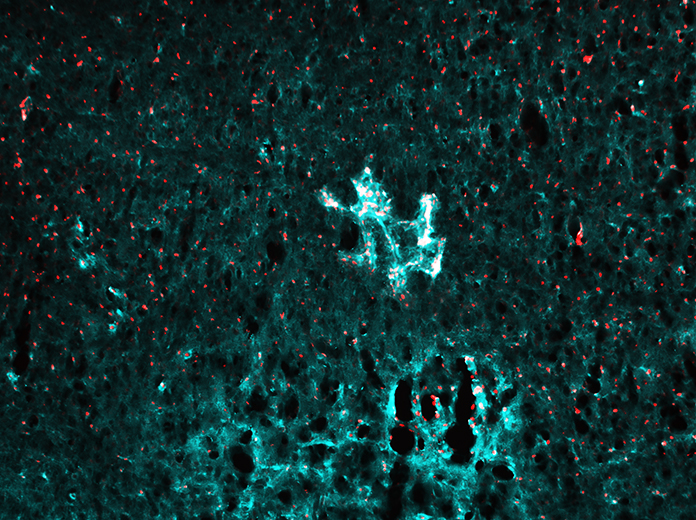

Brain cholesterol